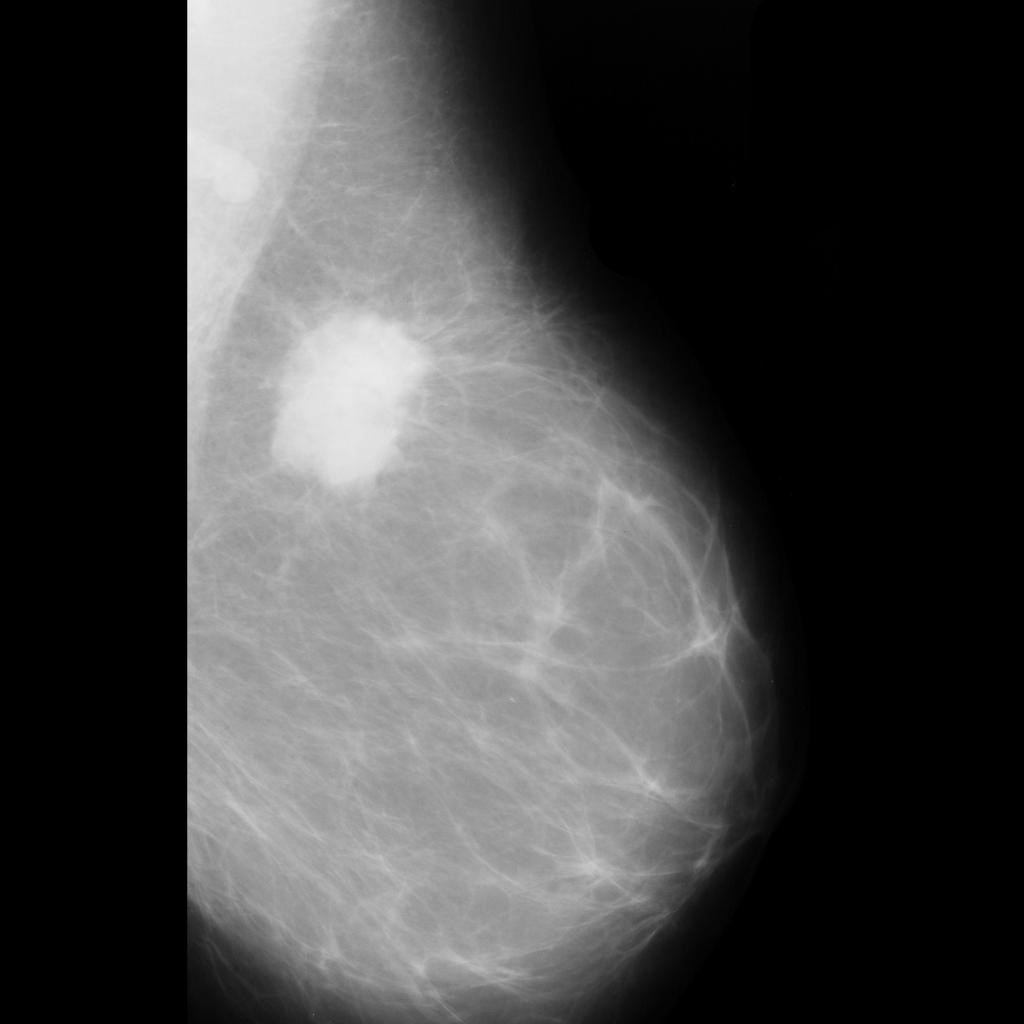

benign

malignant